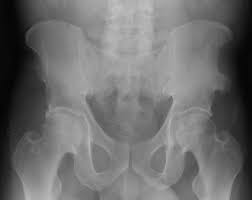

What is pelvis avulsion fracture?1. An avulsion fracture occurs when a tendon or ligament attached to a bone pulls against it and fractures off a piece of the bone. A pelvic fracture is a disruption of the bony structures of the pelvis. Your doctor might recommend that you use crutches to keep weight off the hip while it heals. A pelvic avulsion fracture is where the tendon comes away from the bone, often taking a piece of bone with it.

Pelvic avulsion fractures are usually caused by activities or sports that need speed and sudden stops. Though more common in children, athletic adults are also prone to avulsion fractures. Other sites in the upper extremity involve the humerus and include the greater and. A pelvic avulsion fracture is where the tendon comes away from the bone, often taking a piece of bone with it. Avulsion fractures are caused by trauma. Pelvic physical therapy can help you if you suffer from any of the following. They include pelvic ring fractures [significance of physical examination and radiography of the pelvis during treatment in the shock. In adults, the ligaments and tendons tend to be injured first, whereas in children the bone may fail before. Apophyseal avulsion fractures are usually the result of a sudden forceful concentric or eccentric contraction of the muscle attached to the apophysis. Physical exam should not be used to rule out a pelvic fracture in unconscious patients, but it can nearly definitively rule it in. They usually happen when a bone is moving one way, and a tendon or ligament is suddenly pulled the opposite way. Patients and families need to be counseled about this. Many hip fractures can be treated with physical therapy, rest, or injections.

A pelvic fracture is a disruption of the bony structures of the pelvis. Avulsion fractures are most common in the pelvis. Detailed explanation of pelvis avulsion fracture or avulsion fracture of the pelvis. Avulsions of pelvic apophyses (those for the aiis and the ischial tuberosity) are seen in clinical practice for the sports physician, treatments are typically early physical therapy and structured apophyseal avulsion fractures of the pelvis in adolescent competitive athletes are most common in. Pelvic floor physical therapy plays a key role in calming and desensitizing the central nervous system, and as such, it is considered the gold standard treatment. In this series, nearly all pelvic avulsion fractures (97%) were managed successfully with a conservative approach. The hip, elbow and ankle are the most common locations for avulsion fractures in the young athlete. Falguni vashi pt, dpt, prpc founder of pelvicure physical therapy. An avulsion fracture is an injury to the bone in a location where a tendon or ligament attaches to the bone. An avulsion fracture occurs when a tendon or ligament attached to a bone pulls against it and fractures off a piece of the bone. Physical therapy can also help improve strength and decrease your risk for loss of function. Patients and families need to be counseled about this. Your doctor might recommend that you use crutches to keep weight off the hip while it heals.